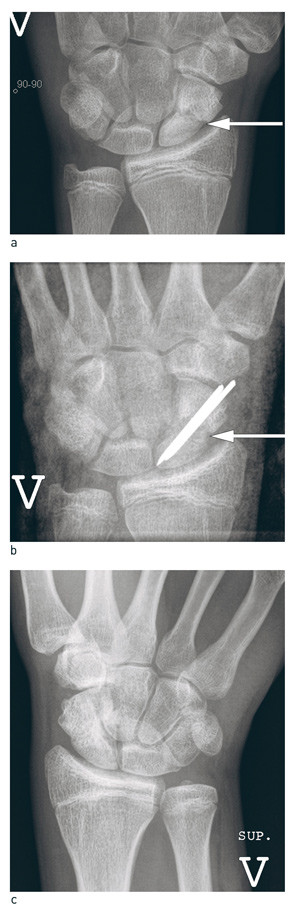

Det er konsensus om at skafoidpseudartroser i midtre og distale del uten artroseforandringer bør opereres med avaskulær beintransplantasjon fra crista iliaca eller distale radius, intern fiksasjon med metallpinner eller skruer (fig 5). Det sikreste er å ha gips i 12 uker postoperativt. 85 – 95 % tilheler, pasientene angir lite smerter og oppnår utmerket håndleddsfunksjon, men ledsagende artrose gir reduksjon i funksjon (36) – (38). Lavere tilhelingsfrekvens er beskrevet ved foreldede metoder, der det kun transplanteres bein uten samtidig intern fiksasjon (39). Det er gjennomført to prospektive randomiserte studier av skafoidpseudartroser der stilket vaskularisert radiusbeintransplantat ble sammenliknet med avaskulært cristatransplantat og avaskulært radiustransplantat. Pasientene i den første studien ble gipset i fire uker, og tilhelingsfrekvensen for avaskulært beintransplantat (73 %) var lavere enn for vaskulært beintransplantat (89 %), men også lavere enn i de fleste retrospektive studiene der pasientene gipses i 8 – 12 uker. Studien har ikke ført til endring i valg av beintransplantat ved pseudartrosebehandling (40). I den andre studien var tilhelingsfrekvensen lik, og gevinsten av vaskulært beintransplantat var for liten og kunne ikke legitimere den mer omfattende og teknisk krevende prosedyren (41).